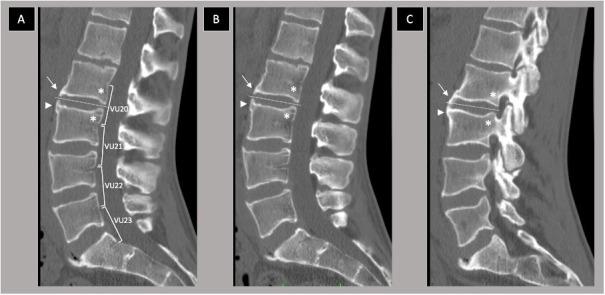

In this paper, illustrations of the different grades and views of the CTSS are presented. CTSS is used to measure bone formation in the spine of patients with axial spondyloarthritis (axSpA), in the form of syndesmophytes. In both the sagittal and coronal planes, syndesmophytes can be graded from 0 to 3 over 23 vertebral units starting at C2 and ending at S1. The CTSS ranges from 0 (absence of axSpA-related syndesmophytes) to 552 (total ankylosis of the spine).

The current atlas contains low-dose CT images of the spine without lesions (for reference) and all grades of syndesmophytes in different planes used in the CTSS. Examples are arranged per spinal segment (cervical, thoracic and lumbar).

本文展示了不同 CTSS 分级和视图的图像。CTSS 用于测量 axSpA 患者脊柱中的骨形成情况,以骨桥的形式表现。在矢状面和冠状面,从 C2 到 S1 的 23 个椎体单元上,骨桥可从 0 级到 3 级进行分级。CTSS 的范围从 0(无 axSpA 相关的骨桥)到 552(脊柱完全强直)。

目前的图谱包含无病变的脊柱低剂量 CT 图像(供参考),以及 CTSS 中不同平面的所有骨桥分级。示例按脊柱节段(颈椎、胸椎和腰椎)排列。